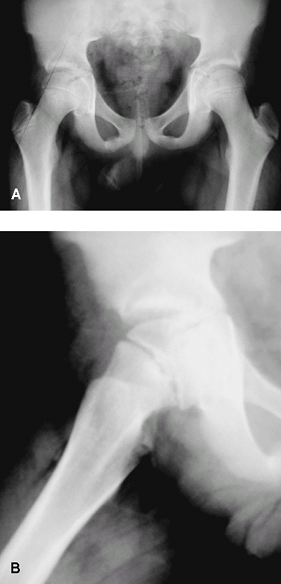

Fig. 1. SCFE occurs through the growth plate, as seen in the right hip here.

Fig. 2. Subtle (grade 1) SCFE. A: Note the subtle loss or epiphyseal height on the right hip and the greater lucency at the physis. B: Slip is more obvious on the lateral view.